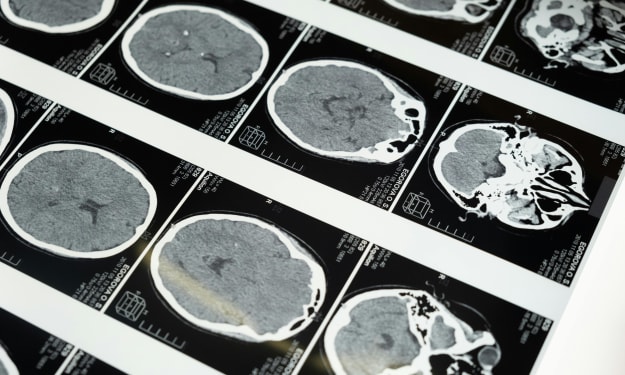

To get processed here it's extremely important to mention the differences between seizures and epilepsy because they're often confused for one another and they are not one in the same seizures broadly speaking are going to be a sudden surge of electrical activity in the cortex of the brain, epilepsy on the other hand is a disease involving recurrent unprovoked seizures meaning we don't know what causes them.

But there are multiples of them so that means that you can have seizures but not suffer from epilepsy meaning there are non-epileptic seizures and epileptic seizures in an epileptic seizure what we see is that sudden surge of electrical activity in the cortex of the brain but we have no idea what's causing it , there are theories and hypotheses and we do have some ideas in some cases.

We don't know what causes that but we see that electrical activity occurring with the use of an electroencephalogram or an eeg and that's going to be very important to the diagnosis of epilepsy in a non-epileptic seizure this is a provoked seizure so we're going to discuss this in greater detail in a moment but let's say just for example you get hit very hard in the head

Seizure and then you even have medications or substances as a cause so or maybe even just withdrawing from the substance, a lot of people out there understand that alcoholics when they are going through withdrawals they can actually be more prone to seizures then we have blood-related causes this is going to be things like a stroke high blood pressure or even brain bleeds like we previously discussed , it is also going to cause in having fever .